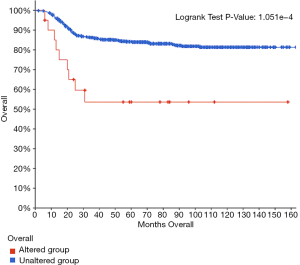

Survival analysis

To investigate the prognostic role of the aberrant TP53 signaling pathway in WT, we used cBioPortal to perform survival curve analysis. The results indicated that the group with alterations had shorter overall survival than the group without alterations (Figure 10), suggesting that the TP53 signaling pathway plays an important role in WT.